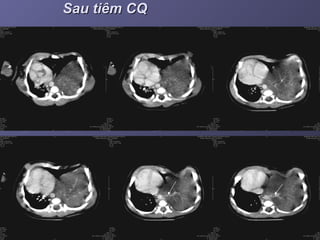

Chụp CT scanner có CQTMChụp CT scanner có CQTM

Sau tiêm CQSau tiêm CQ

- Chụp CT scannerChụp CT scanner (++90%): tiêm cản(++90%): tiêm cản

quang, đa dãy, dựng hình MPR, 3D mạchquang, đa dãy, dựng hình MPR, 3D mạch

máu.máu.

. Là khối choán chỗ đậm độ mô mềm,+_. Là khối choán chỗ đậm độ mô mềm,+_

đồng nhất, ++ cạnh sống trái, +_ dạng ‘tổđồng nhất, ++ cạnh sống trái, +_ dạng ‘tổ

ong’, nang khí or mức khí – dịch. Sau tiêmong’, nang khí or mức khí – dịch. Sau tiêm

cản quang, tăng tỉ trọng không đều, thấycản quang, tăng tỉ trọng không đều, thấy

rõ mạch máu nuôi.rõ mạch máu nuôi.

- Chụp CTscannerChụp CT scanner (++90%): tiêm cản(++90%): tiêm cản quang, đa dãy, dựng hình MPR, 3D mạchquang, đa dãy, dựng hình MPR, 3D mạch máu.máu. . Là khối choán chỗ đậm độ mô mềm,+_. Là khối choán chỗ đậm độ mô mềm,+_ đồng nhất, ++ cạnh sống trái, +_ dạng ‘tổđồng nhất, ++ cạnh sống trái, +_ dạng ‘tổ ong’, nang khí or mức khí – dịch. Sau tiêmong’, nang khí or mức khí – dịch. Sau tiêm cản quang, tăng tỉ trọng không đều, thấycản quang, tăng tỉ trọng không đều, thấy rõ mạch máu nuôi.rõ mạch máu nuôi.